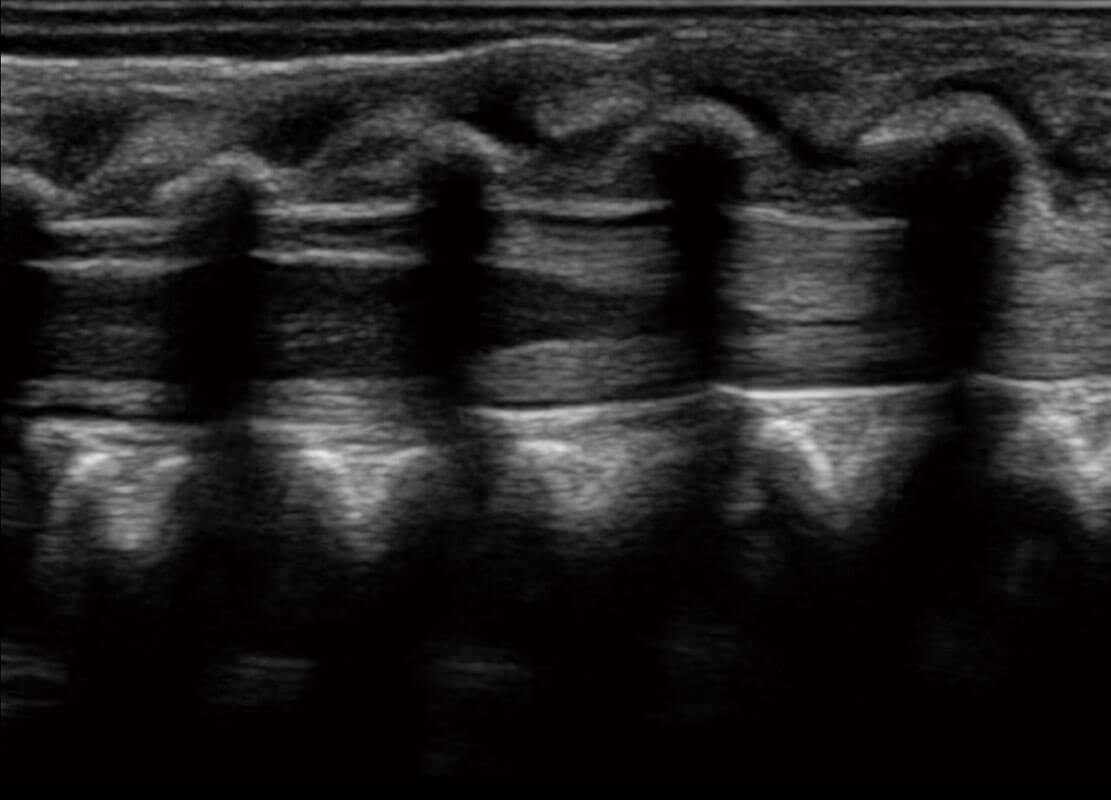

生殖健康

P60优异的图像质量搭载专科探头,在妇科基础疾病的诊断、卵泡生长的监测、输卵管通畅情况的判别等方面为您提供生殖应用方案。

• 腔内妇科-宫腔分离

• 腔内妇科-卵巢